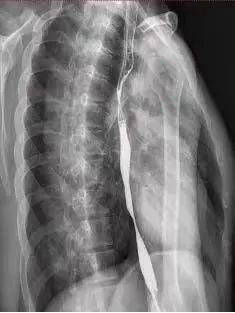

完成3次手术后,小蔡食管狭窄的问题总算得到解决,吞咽不畅的情况完全消失,终于可以“大口吃肉”了。

▲小蔡如今的食管

▲小蔡如今的食管医生提醒: